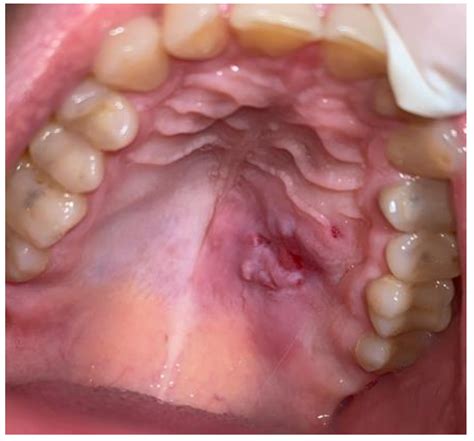

• Burn Mouth Syndrome (BMS): A complex condition characterized by a chronic, unexplained burn sensation in the mouth without an obvious physical wound.

Burning Mouth Syndrome Chronic burning, no visible injury Long-term/Chronic

• Recurrent Symptom: If you frequently know a burning sensation without an obvious external cause, it may signal a systemic issue like diabetes, thyroidal disfunction, or hormonal alteration.

• Unexplained Maculation: Any persistent discolouration, lump, or firm patches on the palate that do not disappear require a biopsy or professional evaluation.